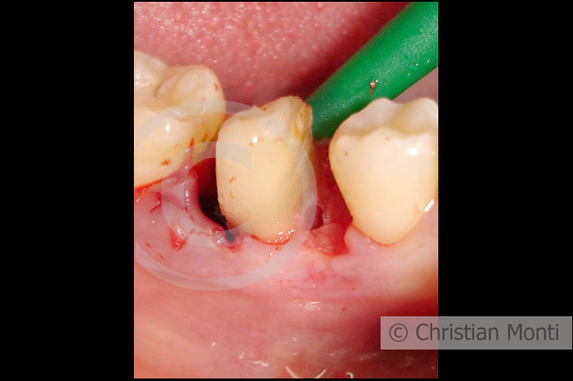

EDENTULIA SINGOLA

Impianto dilazionato in sostituzione di un molare inferiore